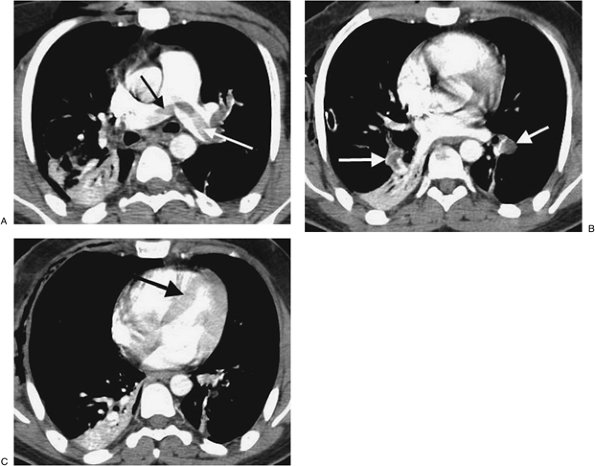

FIGURE 17-7. Acute PE. CTPA of a 76-year-old man with acute shortness of breath shows a large intraluminal filling defect within the proximal right lower lobe pulmonary artery (solid arrow) and a smaller intraluminal filling defect within a segmental pulmonary artery to the left lower lobe (dashed arrow).

FIGURE 17-8. Acute PE associated with pulmonary arterial hypertension. A: CTPA of a 23-year-old man involved in a motor vehicle crash shows a saddle embolus straddling the right and left main pulmonary arteries (arrows). The central pulmonary arteries are enlarged. B: CTPA at a more inferior level shows thrombus within segmental branches of the lower lobe pulmonary arteries (arrows). C: CTPA at a level inferior to (B) shows leftward bowing of the interventricular septum (arrow).